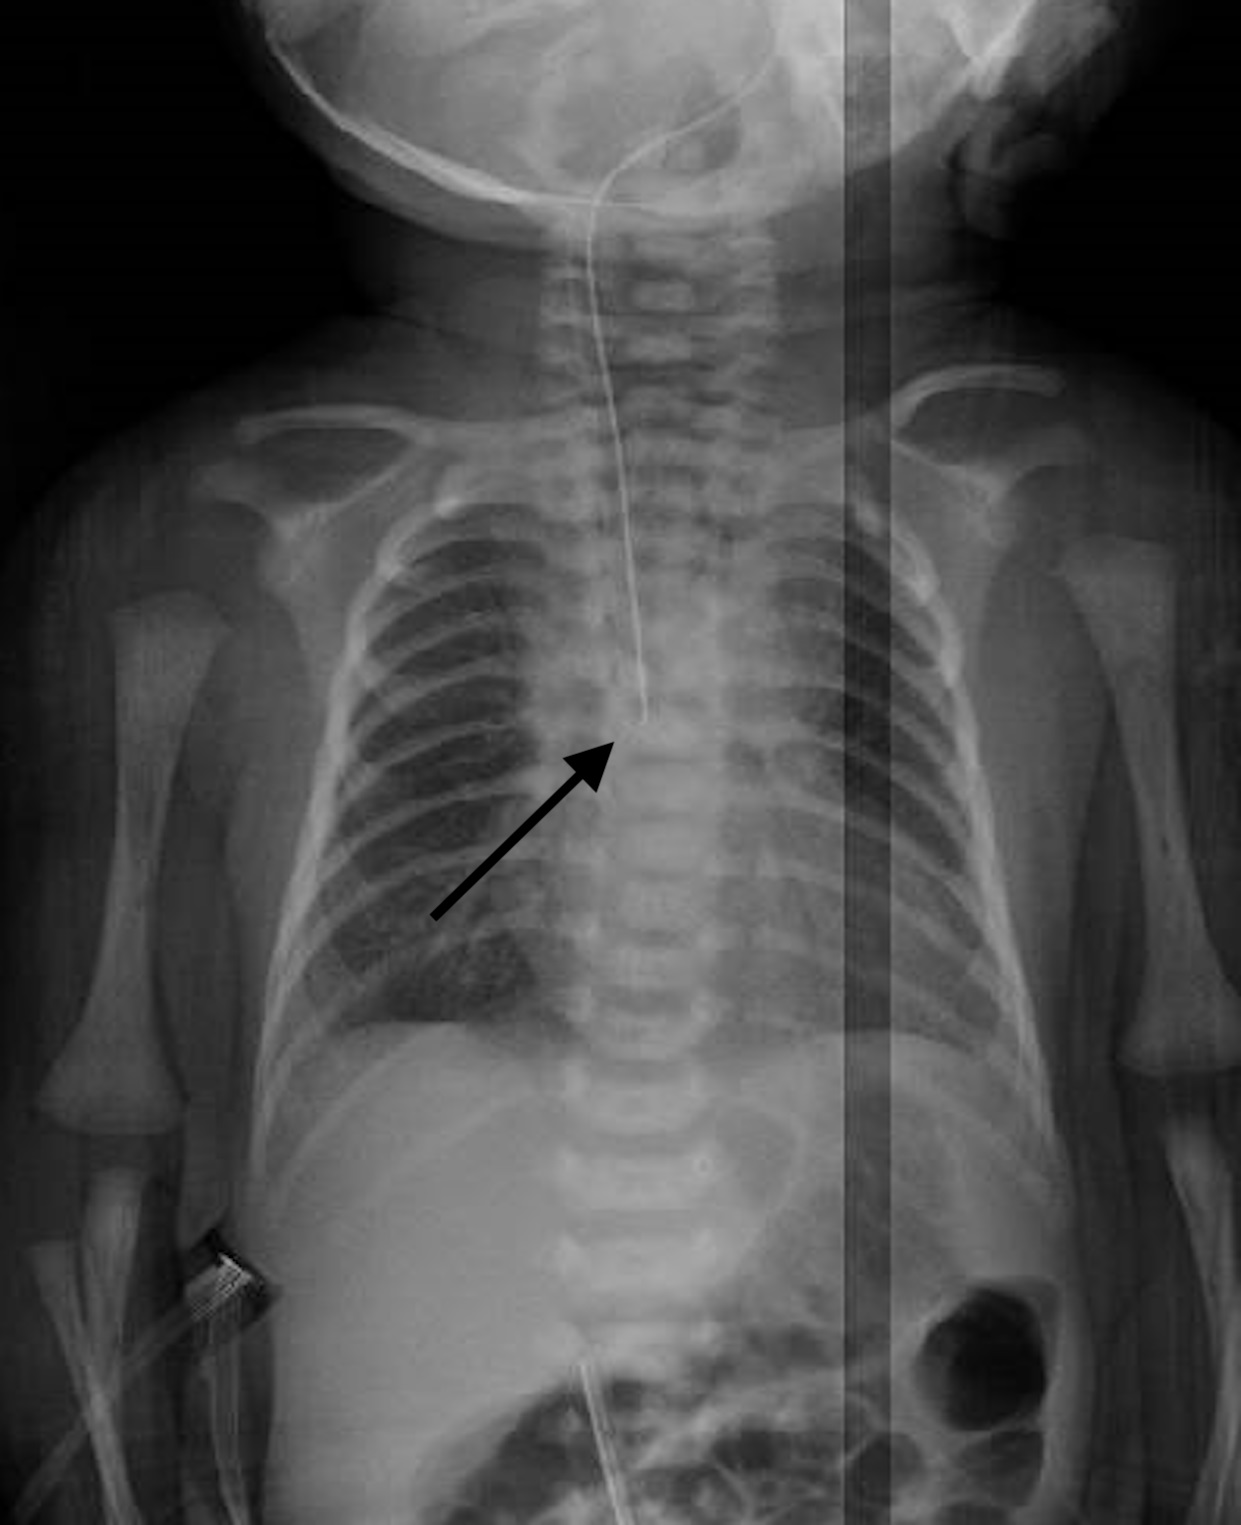

Figure 2

Case 1: Pre-operative esophagram shows opacification of the upper pouch with a minimal mediastinal leak (arrow).